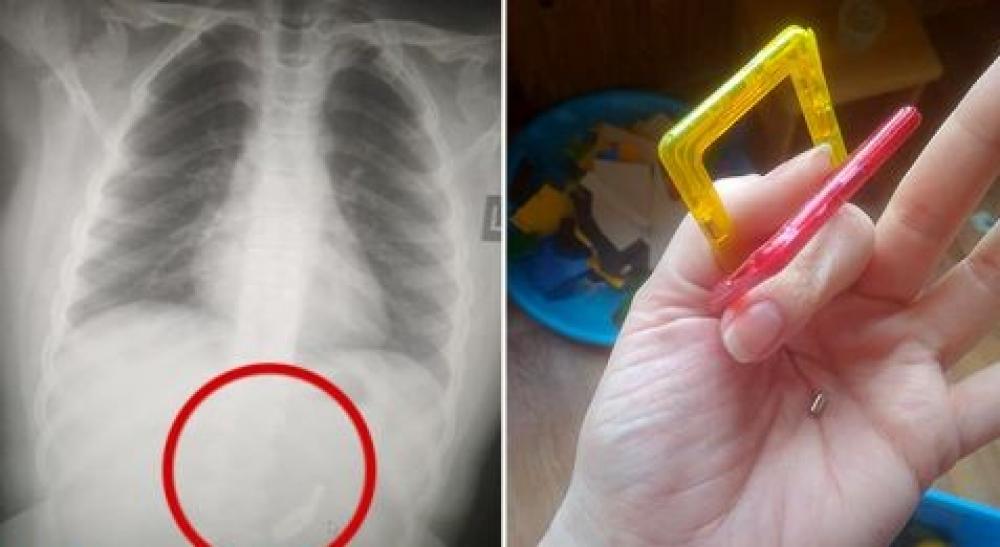

В Одеській області лікарі вже тиждень борються за життя 10-річної дівчинки. Все через вірусне відео у соцмережі, де два круглі магніти використовували як такий собі "пірсинг" з одного та іншого боку язика. Школярка випадково ковтала такий магнітний пірсинг три дні поспіль.

Як вже потім дізналися батьки, донька три дні поспіль ковтала магніти. Для дівчинки це обернулося реанімацією: магніти пошкодили кишківник, дванадцятипалу кишку та шлунок.

Боротися з наслідками навіть за вдалого лікавання доведеться ще довго. Оскільки обов’язково виникає спайкова хвороба, з якою людина бореться все життя та буде переносити не один десяток оперативних втручань.

У Великій Британії вже три роки б'ють на сполох, бо лише за цей час було 65 випадків, коли діти, повторюючи популярний челендж з соціальної мережі, ковтають магніти. Абсолютно всі діти в результаті опинилися в лікарні.